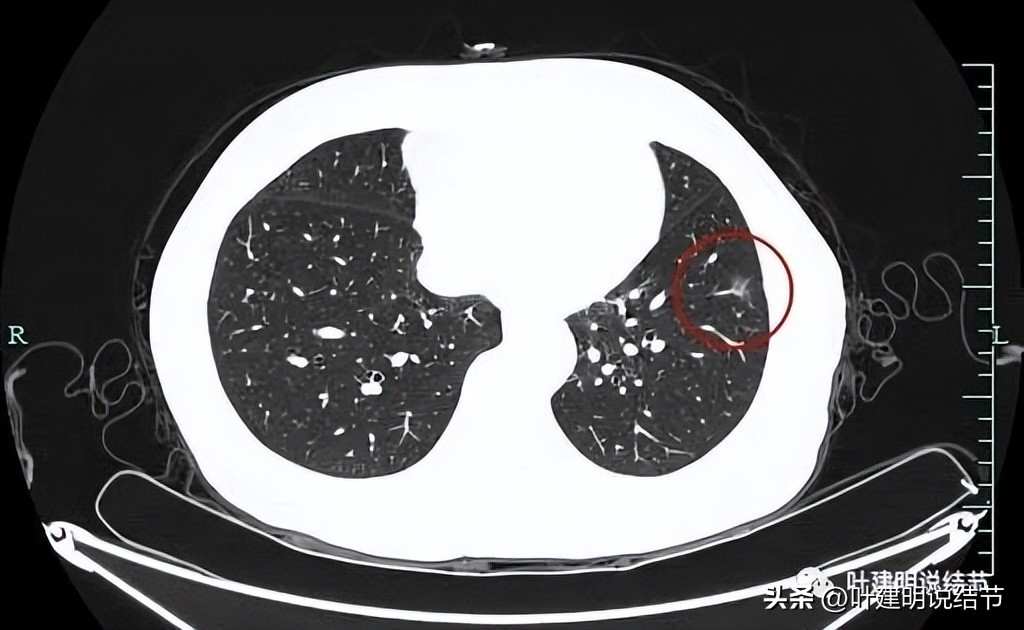

靶重建后发现病灶囊腔型,桔色箭头示进入的血管有异常增粗,而且壁显得毛糙;黄色箭头示空腔;红色箭头示整体轮廓较清;绿色箭头示有磨玻璃成分,虽然密度较低;蓝色箭头示病灶略有胸膜牵拉影响,只是力较弱而已。

上图显示了病灶轮廓与瘤肺边界其实还是清楚的。

部分边缘有毛刺征可见。

显示明显的血管征与血管异常增粗和壁毛糙。

上图显示病灶轮廓较清,有锐利细毛刺征,灶内有弯曲血管穿行。

囊壁有少许是偏实性成分的,如粉色箭头所示。

血管增粗进入并散开来。

血管在病灶内发出分支。